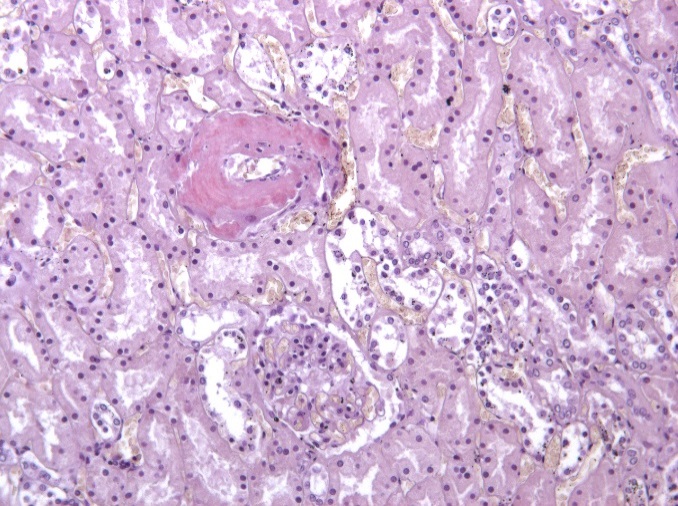

Гистологическое исследование. Сердце – кардиомиоциты гипертрофированы, диффузный кардиосклероз. При окраске на амилоид в строме и стенке сосудов отложение амилоидных масс (рис. 1). Селезенка – красная пульпа полностью замещена однородными массами, дающими положительную окраску на амилоид (рис. 2).

Почки – резкое уменьшение числа клубочков, отдельные полностью замещены однородной массой, дающей положительную реакцию на амилоид (рис. 3). В стенке сосудов также видны отложения амилоида (рис. 4).

Рис. 4. Амилоид в стенке сосуда в почке. Окраска конго красный, ×200